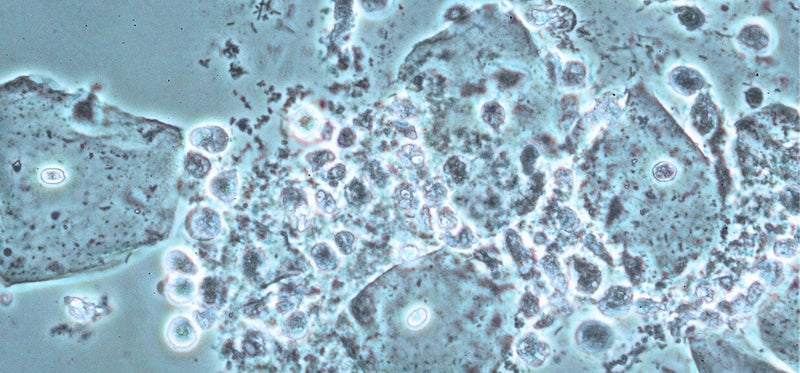

Urinalysis is typically the first test performed. It’s the classic “pee in a cup” test that examines a urine sample for signs of infection, including the presence of white blood cells (which indicate your body is fighting an infection), red blood cells (which may suggest irritation or damage to the urinary tract), and bacteria. The test can also detect nitrites, which are produced by certain bacteria commonly responsible for UTIs.